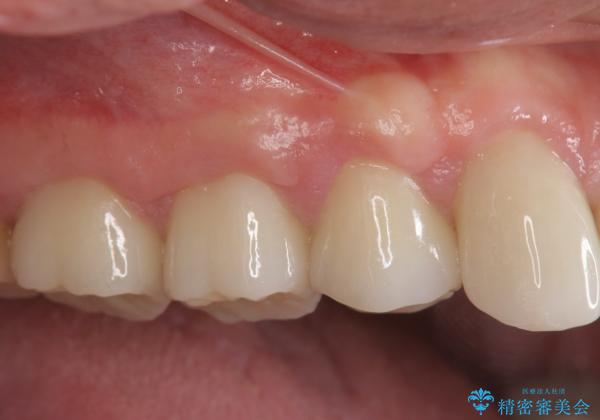

歯周外科で達成する安定したクラウン周囲の歯肉環境

すり減ってしまった歯に対し、歯冠長延長術(歯周外科)を行うことで安定したクラウンを製作・装着することが出来ました。